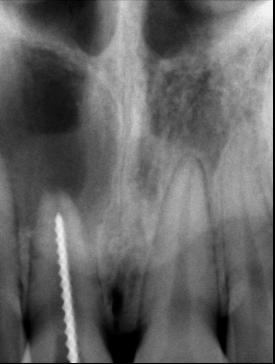

En la radiografía lateral de cráneo ( Figura 6 ) se ve la línea estética de Rickets, que el labio superior se encuentra a +0.5 mm y el inferior a -2 mm. En las mediciones cefalométricas más importantes en la figura 11 un ANB de 5º, GoGn-SN de 33º y FMA de 21º crecimiento normodivergente y Witts de -1 mm. A los criterios dentales encontramos

1-PLT de 129º e IMPA 99º proinclinación de incisivos tanto superiores como inferiores. En la radiografía panorámica (Figura 7), la presencia de 32 órganos dentarios, con terceros molares inferiores aún sin erupcionar y terceros molares superiores

7. Radiografía panorámica.

Figura 8. Cortes sagital, inclinaciones dentales superior e inferior, axial tomográfico de las arcadas.

Figura

de clase II esquelética y dental

ya erupcionados, falta de paralelismo radicular, asimetría condilar, articulación temporomandibular (ATM) izquierda afectada.

Secuencia de radiografías laterales de cráneo (Figura 15) vemos que el ANB disminuyo 1º de inicio a fin clase I con tendencia a clase II esquelética a final. Reducción de Witts 0.5 mm final, crecimiento normodivergente. Mandíbula más pequeña que el maxilar, cambio por el avance mandibular.

Panorámicas de inicio a fin (Figura 16) el paralelismo radicular, genera estabilidad a largo plazo en el tratamiento. Se extrajeron los terceros molares para eliminar discrepancia posterior y lograr adecuada

Figura 16. Radiografías panorámicas. a) Inicio. b) Progreso. c) Final.